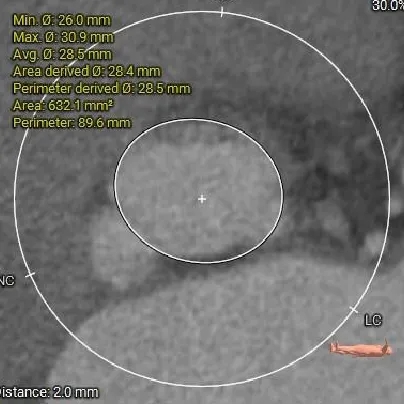

瓣上结构测量

瓣上2mm

28.5mm

瓣上空间逐渐增大,仅瓣上2mm左右可提供锚定